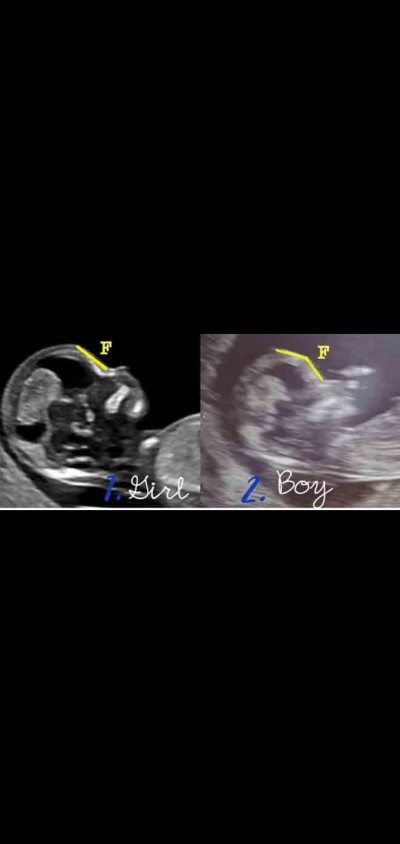

aranız da cinsiyet tahmininde bulunacak var mi 12. Haftada genelde tahminde bulunuyolarmis fakat bana Bi tahmin söylemediler devlette. Aranızda tahmini olan var mi

Gebelik haftası 12

kKız bebek büyük ihtimal urafe ama bende tuttu

İnternnet görmüştüm 11_13.hafta bebeğin alın yapısı düz ise kız köşeli ise erkek diyorlardı. Ama doğrumu değil mi bilmiyorum. Doktorlara göre kemik yapısından belli olmaz.